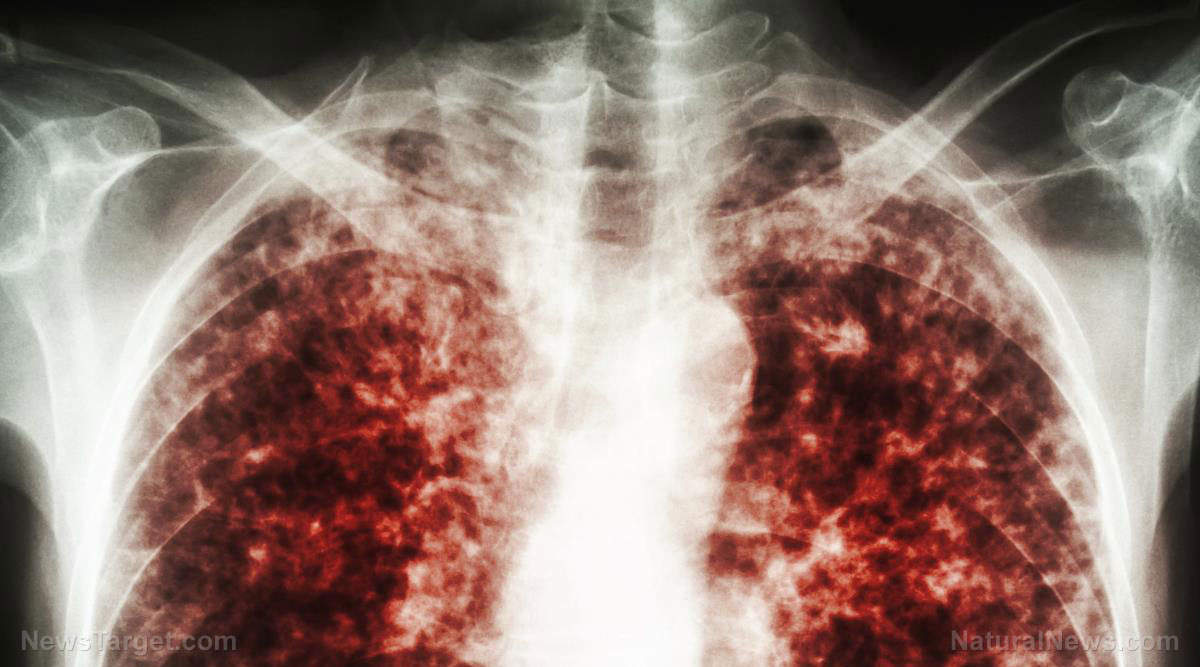

The Vaccine Cult of Insanity is flying off the rails as RFK Jr. blows the whistle on the deadly, turbo-cancer-causing COVID CLOT SHOTS at hearings

Peer-reviewed study links COVID vaccines to “profound harm,” raises concerns over gain-of-function research

South Korean study links COVID-19 vaccines to increased risk of 6 cancers